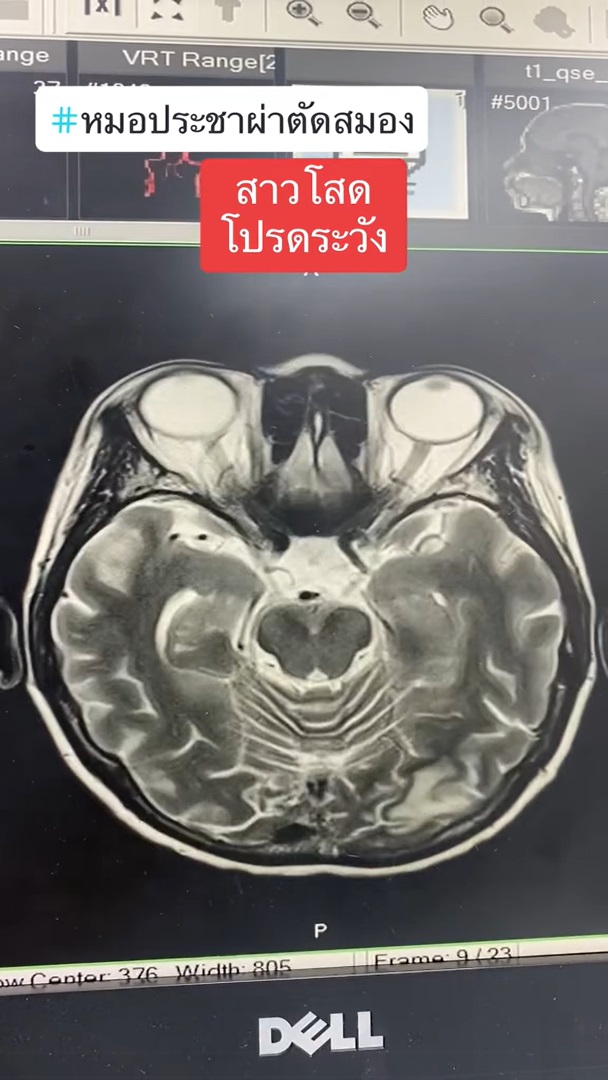

ทำเอาเหล่าสาวโสดถึงกับร้อน ๆ หนาว ๆ หลังจากที่ นายแพทย์ประชา กัญญาประสิทธิ์ หมอผ่าตัดสมอง ออกมาโพสต์เตือนภัยใกล้ตัวที่มีแนวโน้มจะเกิดกับสาวโสดได้ง่ายกว่าคนที่มีลูก โดยได้ยกเคสผ่าตัดเคสหนึ่งมาเป็นกรณีศึกษา ระบุว่า มีผู้ป่วยหญิง อายุ 57 ปี เป็นสาวโสดอยู่คนเดียว มาหาหมอด้วยอาการพูดจาสับสน ซึ่งผลการตรวจเอกซเรย์ พบว่า มีสมองตายหลายจุด ตายทั้งข้างหน้า ข้างหลัง ลามไปจนถึงท้ายทอย ทำให้ตามัว และมีจุดเลือดออกในหย่อมที่สมองตายด้วย และยังตรวจพบอีกหลายอย่าง อาทิ

แคลเซียมก็สูงมาก จากลักษณะของมะเร็ง ไม่ใช่กระจายไปที่สมอง ลิ่มเลือดอุดตันที่ขาสองข้าง ทำให้ขาบวม ทั้งยังเกิดลิ่มเลือดอุดตันในสมองหลายตำแหน่ง คนไข้จึงมาด้วยอาการพูดจาสับสน สุดท้ายกลายเป็นมะเร็งรังไข่ ซึ่งเคสนี้ก็ต้องผ่าตัดและสู้กับมะเร็งรังไข่กันต่อไป